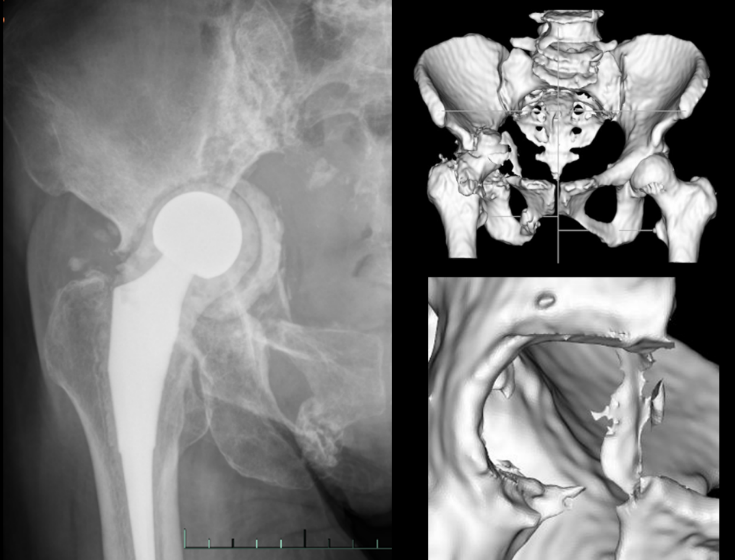

Imaging one year post-spacer surgery of the right hip joint

Post-operative imaging